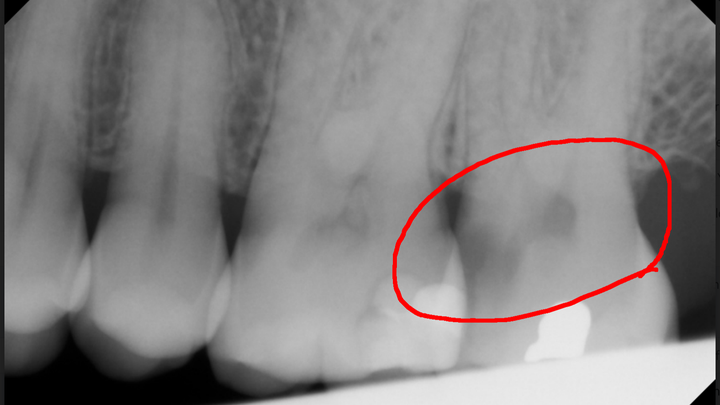

She fears there may be complications, but she is not sure.